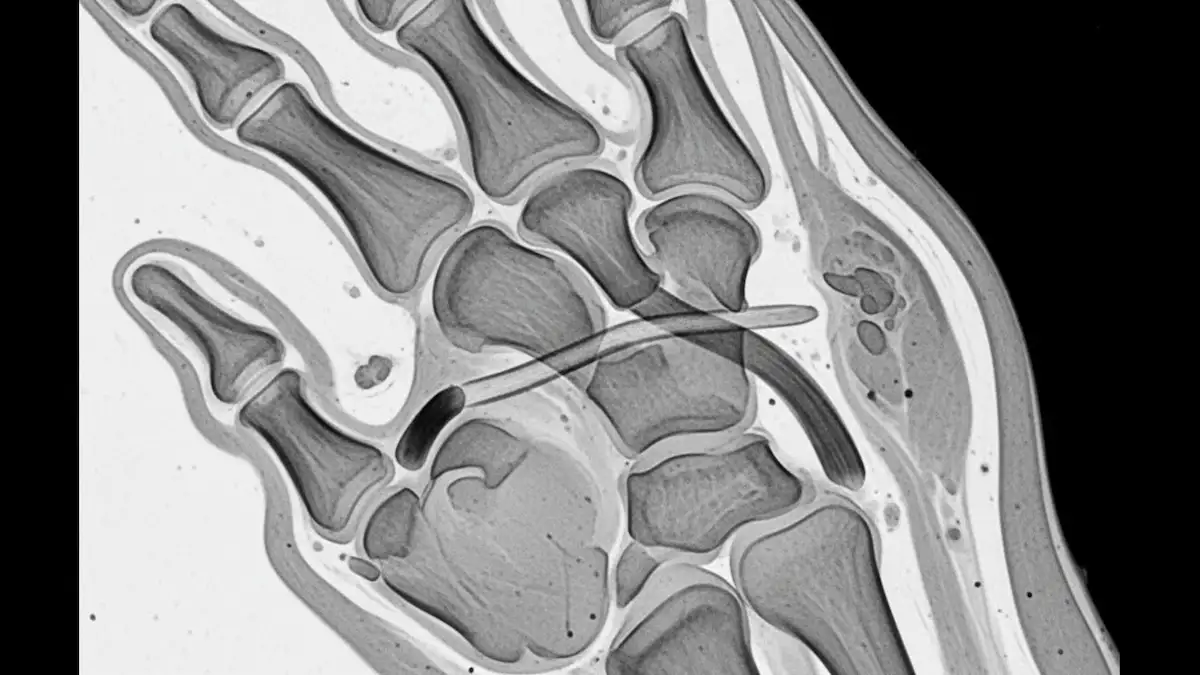

Já o ultrassom e a ressonância magnética conseguem avaliar o ligamento e podem identificar se existe deslocamento compatível com lesão de Stener.

A ressonância costuma dar uma visão mais completa, com maior custo e, às vezes, mais demora para agendar.